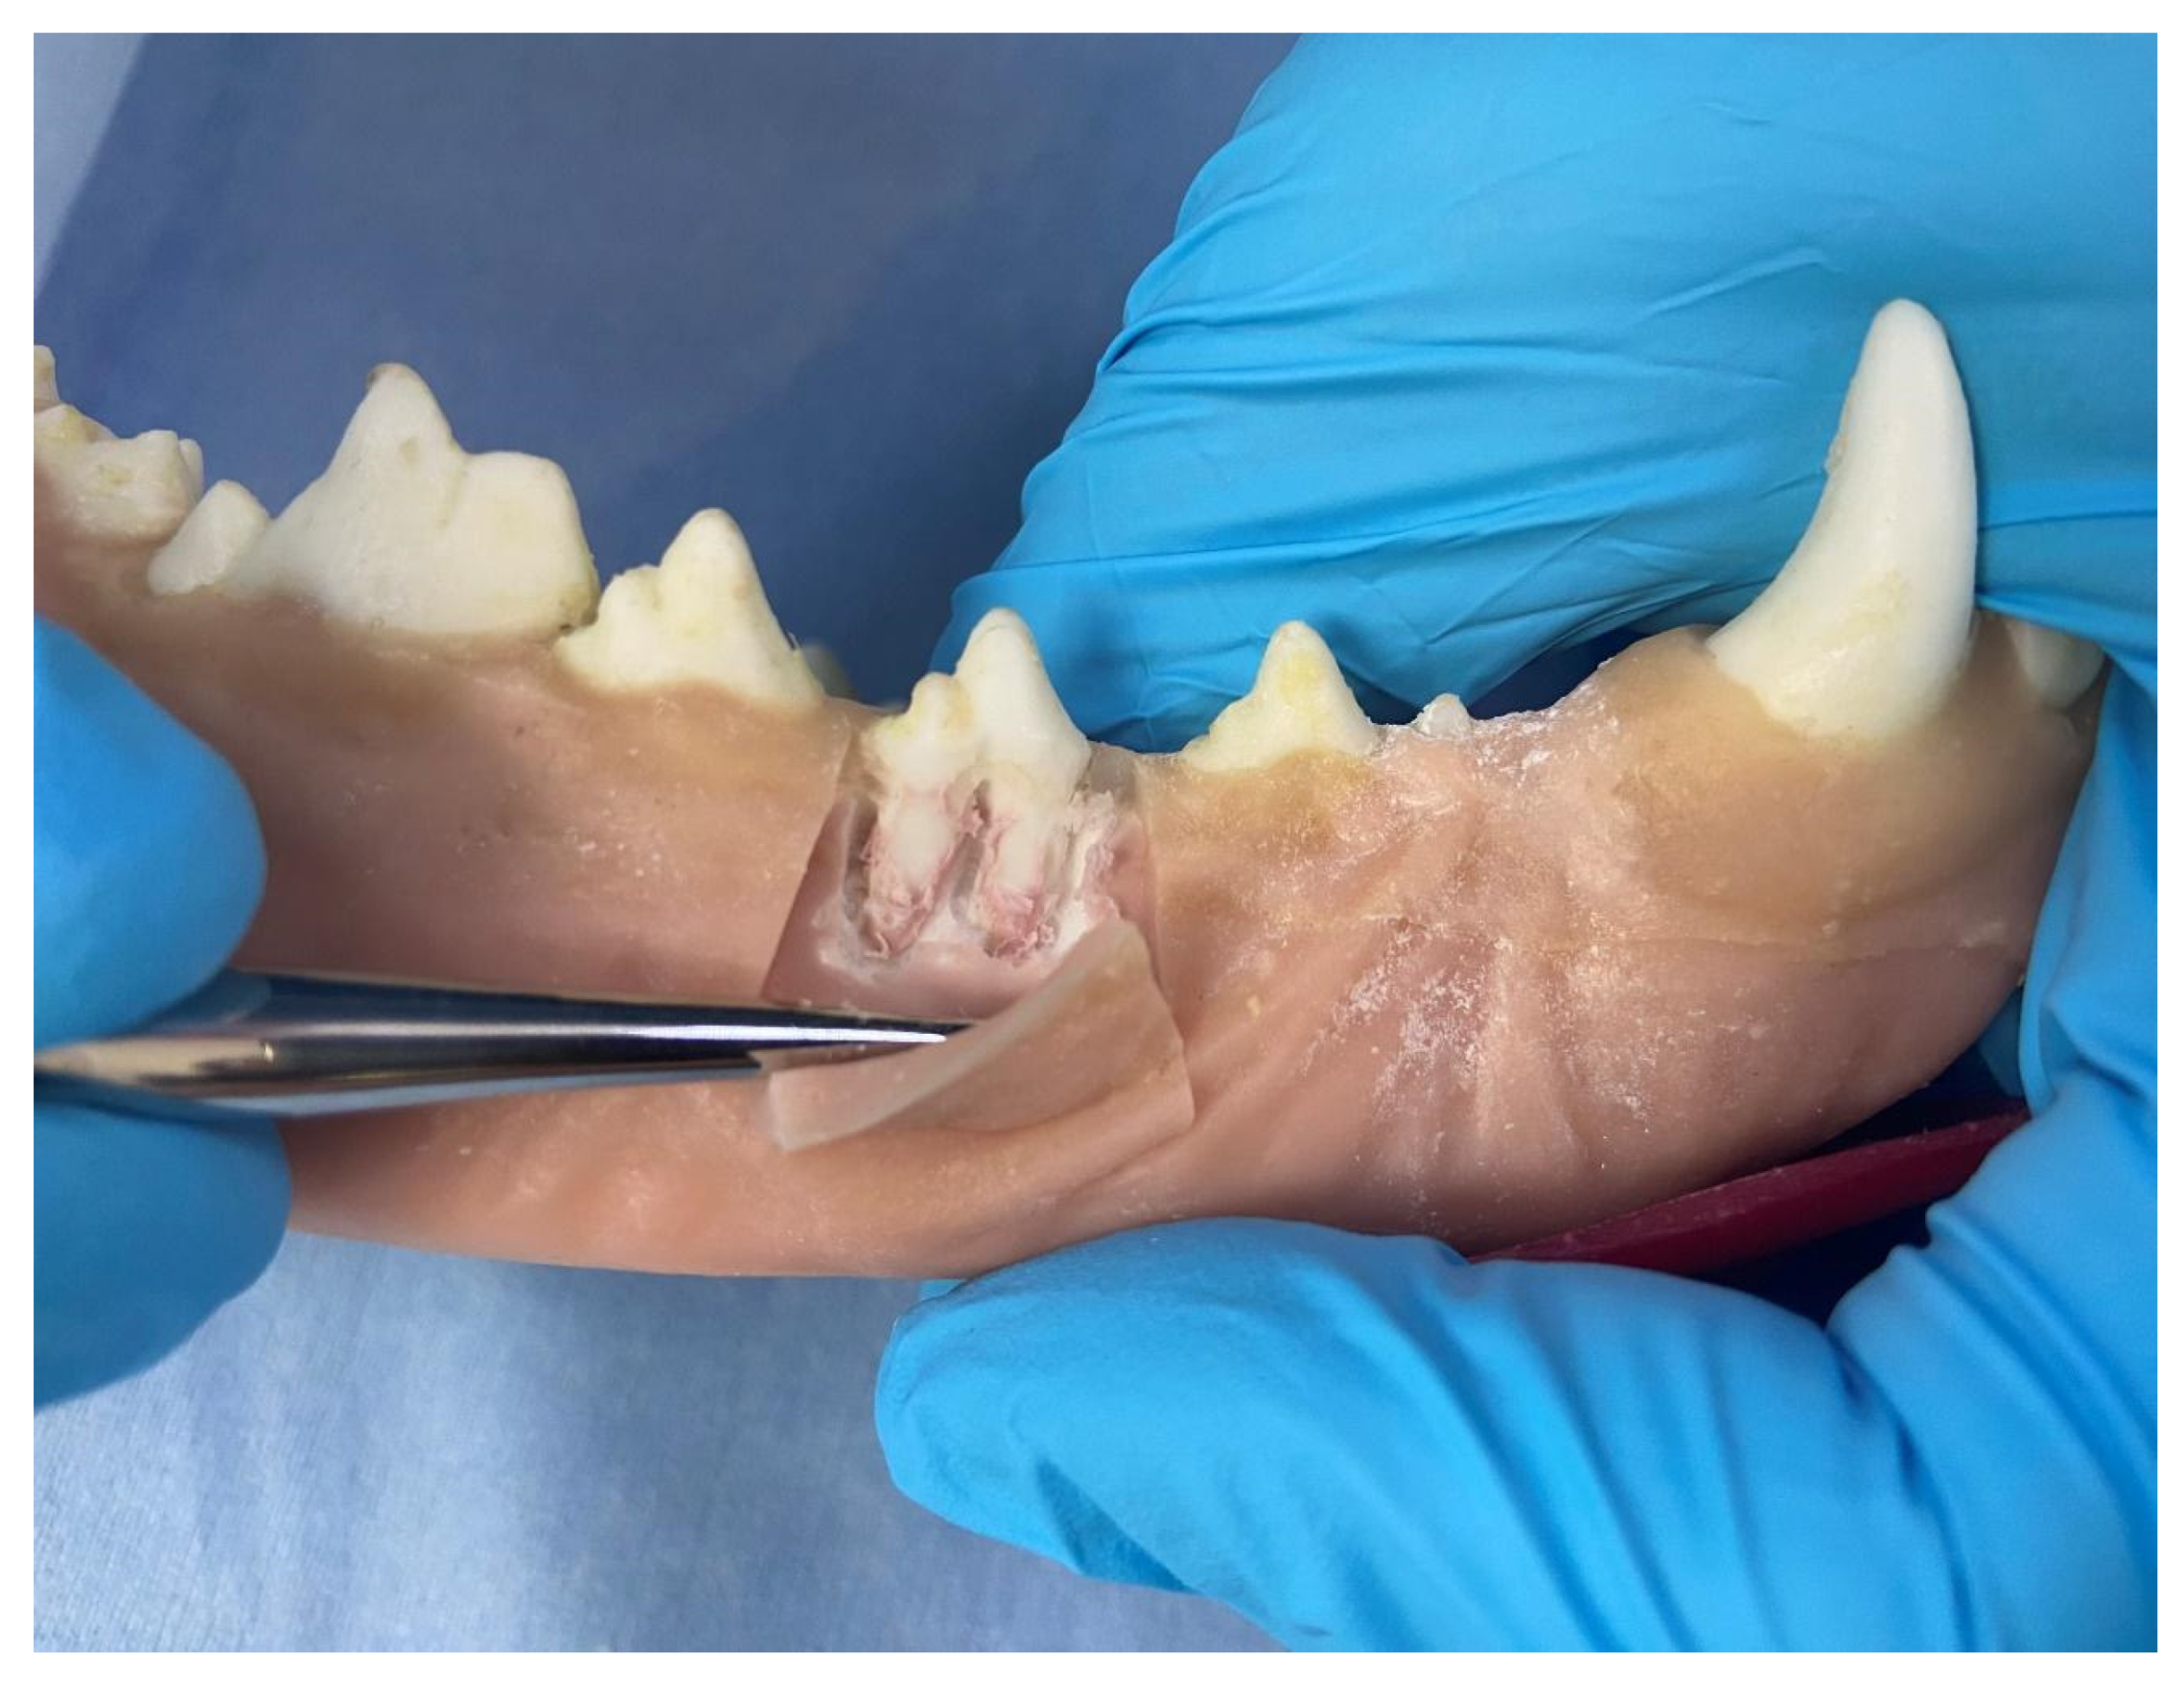

At the time the study was conducted, three sets of jaws were available for use to teach different skillsets. (i) One set was used to teach scaling and polishing that included simulated calculus painted onto the teeth. Once dry, an ultrasonic scaler could be used to remove the simulated calculus as in a live patient. (ii) A second set with radiodense teeth was used to teach radiographic positioning (Figure 3). (iii) A third set was used to teach extractions, which included a simulated periodontal ligament. These techniques were used to perform gingival flap creation, alveolar bone removal, tooth elevation and tooth extraction (Figure 4). Components were colored in a realistic fashion to allow for the identification of different simulated tissues.

Figure 4. HFM Mandible Demonstrating Gingival Flap and Surgical Extraction Technique.

Vetsci 10 00526 g004